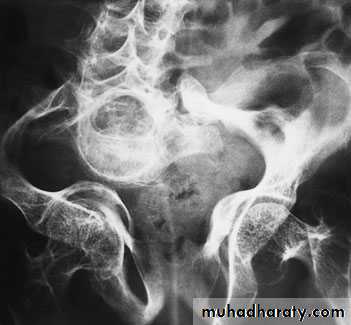

OSTEOGENESIS IMPERFECTA (BRITTLEBONES) (OI)

is one of the commonestof the genetic disorders of bone, with an

incidence of 1 in 20 000. Abnormal synthesis and

structural defects of type I collagen result in

(1) osteopenia,

(2) liability to fracture,

OI TYPE III (SEVERE DEFORMING) •

The ‘classic’, but not the most common, form of OI.• Fractures often present at birth.

• Large skull and wormian bones; pinched-looking

face.

• Marked deformities and kyphoscoliosis by 6 years.